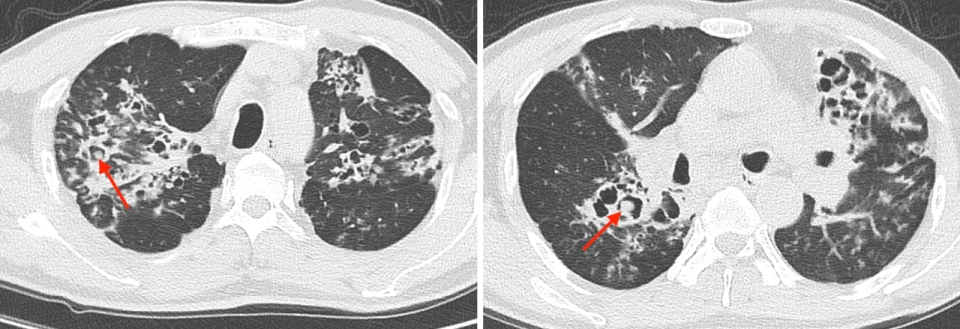

入院 CT 见图 1。

图 1. CT 示两肺广泛散在渗出伴支气管扩张,空洞内有球形结构(箭头)

分析:患者有慢性结构性肺病(支扩)史,长期吸入激素,因咳嗽加重伴发热 1 周入院,CT 影像学可见空洞内球状结构,高度提示肺曲霉球。